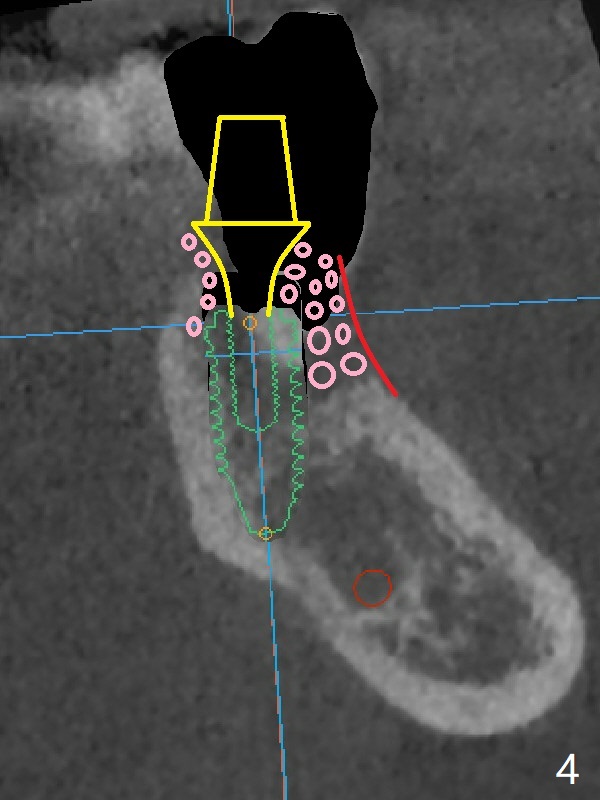

A 67-year-old man requests treatment for the tooth #19 with severe buccal gingival recession (Fig.1). After extraction, a 5x11.5 mm implant will be placed as lingual as possible (Fig.2 L) with ~7 mm buccal implant thread exposure. To reduce the exposure, the implant will be placed deeper, as shown by arrow in Fig.3. PRF membrane and collagen membrane (Fig.4 red line) will be placed against the buccal gingiva, while PRF associated sticky bone (allograft, pink circle) will be packed around the exposed implant threads and a long-cuff abutment (yellow). Finally an immediate provisional (Fig.5 white) will be fabricated to cover the bone graft.